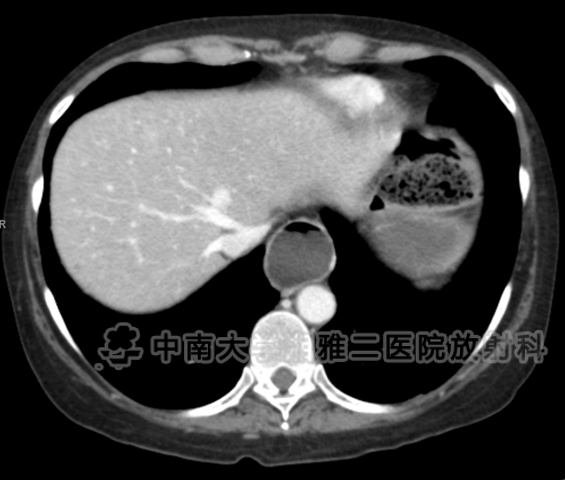

● 女,51岁,便秘。

● 对比增强CT显示食管明显扩张(箭头所示)。

● 在结肠中有明显的粪块残留,在结肠壁(箭头)内存在气体,相关肠壁无增厚或肠系膜脂肪的滞留,与结肠囊样积气一致。

● 在空肠(箭头所示)中有一堆又细又直的褶皱。

● 硬皮病:这是诊断,由食管扩张、粪便滞留、便秘史、结肠囊样积气、小肠皱襞表明。

● 本病例的影像学表现和便秘的临床史强烈提示了硬皮病的诊断,或进行性系统性硬化症。

● 硬皮病被认为是一种自身免疫性的胶原血管疾病,它会影响全身的小血管,导致平滑肌萎缩、纤维化和胶原沉积。90%累及胃肠道和80%累及食道。

● 如本例所见,小肠在皮肤发生变化后,通常小肠出现薄而直的皱褶改变的频率会增高(通常是空肠)。

● 有一半的硬皮病患者会出现便秘,而CT表现为粪便残留,如本例中,结肠扩张为假囊袋样。